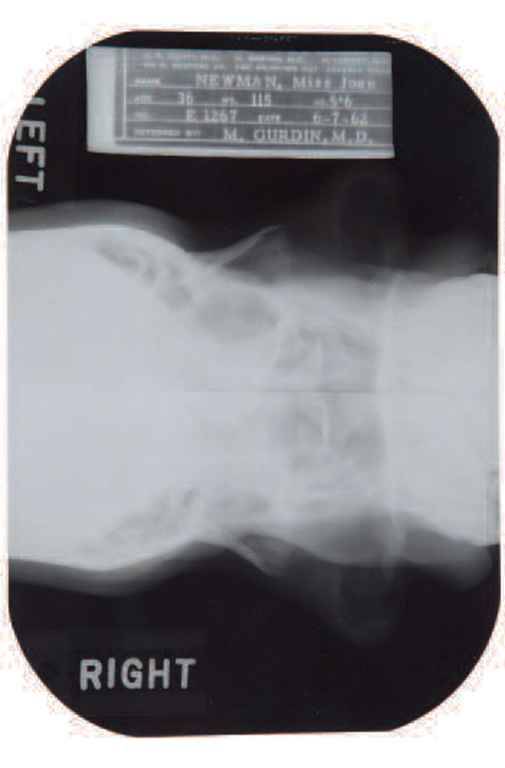

Il pettegolezzo sul ricorso al bisturi sembra infatti trovare conferma dagli appunti di un medico, il defunto dott. Michael Gurdin. Una sorta di ‘cartella sanitaria’ dell’attrice, con tanto di lastre, in cui si fa riferimento ad un intervento estetico al mento e ad una rinoplastica effettuata nel 1950.

I raggi X sono invece del 7 giugno 1962, due mesi prima della sua morte, avvenuta all’eta’ di 36 anni per un’overdose di barbiturici. Le lastre al cranio, alle ossa nasali e al palato, insieme alla documentazione sanitaria della star americana, saranno messe all’asta a Beverly Hills, in California, il prossimo 9 novembre. La base di partenza e’ tra i 15 e i 20 mila dollari.